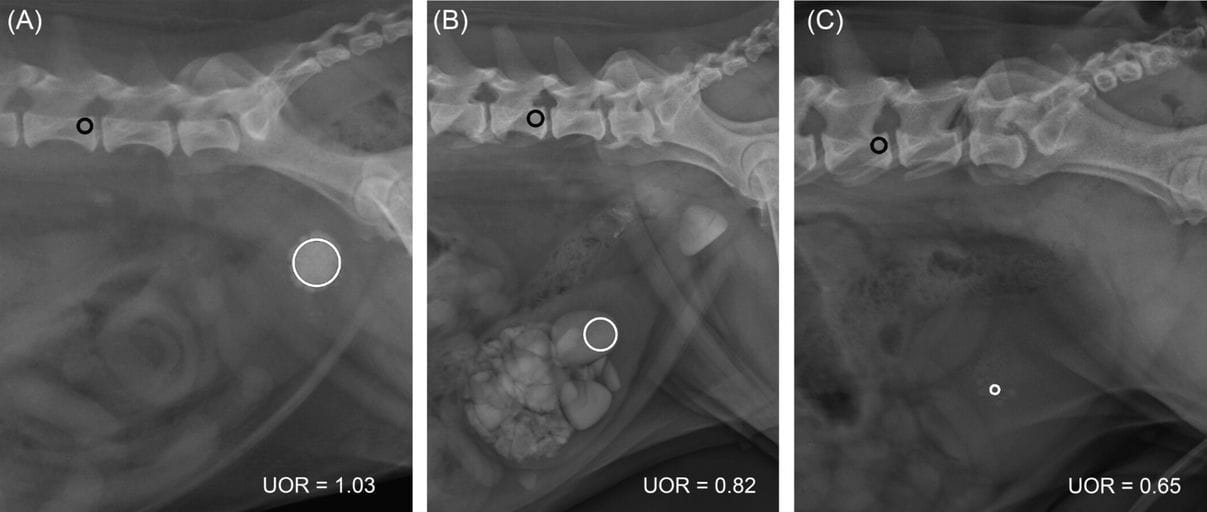

Measurements of the ratio (labeled UOR) of the mean pixel value (MPV) of the largest cystolith to the L5 MPV on lateral abdominal radiographs in three dogs. A circular ROI is positioned at the caudal third of L5 vertebra (black circle) with care to avoid superimposition with cortical bone and vertebral transverse processes, and a circular ROI is placed on the largest cystolith (white circle) with care to incorporate as much of the urolith as possible without including its peripheral margins and to avoid superimposition with other uroliths, digestive structures and potential bubbles of gas due to prior catheterization. (A) Bosselated calcium oxalate cystolith in a dog. The MPV of urolith is 2015; the MPV of L5 is 1952; the UOR value is 1.03. (B) Large pyramidal struvite cystoliths and one similar urethrolith in a dog. The MPV of urolith is 1542; The MPV of L5 is 1875; The UOR value is 0.82. (C) Multiple small faceted cystine cystoliths in a dog. The MPV of urolith is 1253; The MPV of L5 is 1914; The UOR value is 0.65.